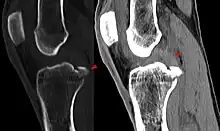

Le décollement ou l'arrachement du LCA de l'os est substantiellement plus rare que la rupture intraligamentaire[5] et n'est pas une rupture de ligament. Ce cas particulier survient plus fréquemment chez les enfants, particulièrement dans le domaine du tubercule intercondylaire du tibia, et possède en général, par refixation de l'arrachement par exemple avec des vis ou des fils métalliques, de bonnes chances de guérison complète.

Les radios n'apportent aucune contribution immédiate au diagnostic de rupture de LC. Les deux LC sont invisibles à la radio, déchirés ou non. La seule utilité de la radio ne peut servir qu'au diagnostic des complications osseuses possibles.